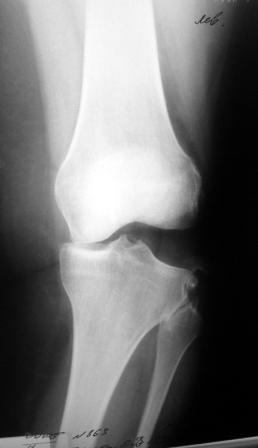

Сегодня на приеме была больная 27 лет, вес 120кг. Травма 7 лет назад -

ДТП. Была ЧМТ, двухсторонний перелом пилона, обширные рваные раны

бедер, голеней. Судя по нынешней картине - вывих голени слева. Ходит

практически не хромая, жалобы на неустойчивость голени при ходьбе. При

стресс тестах - грубейшая несостоятельность связочного аппарата

коленного сустава. Хотелось бы услышать мнение о целесообразности

пластического восстановления связок после столь длительного периода

нестабильности сустава.

Имя     : SDC10834.JPG